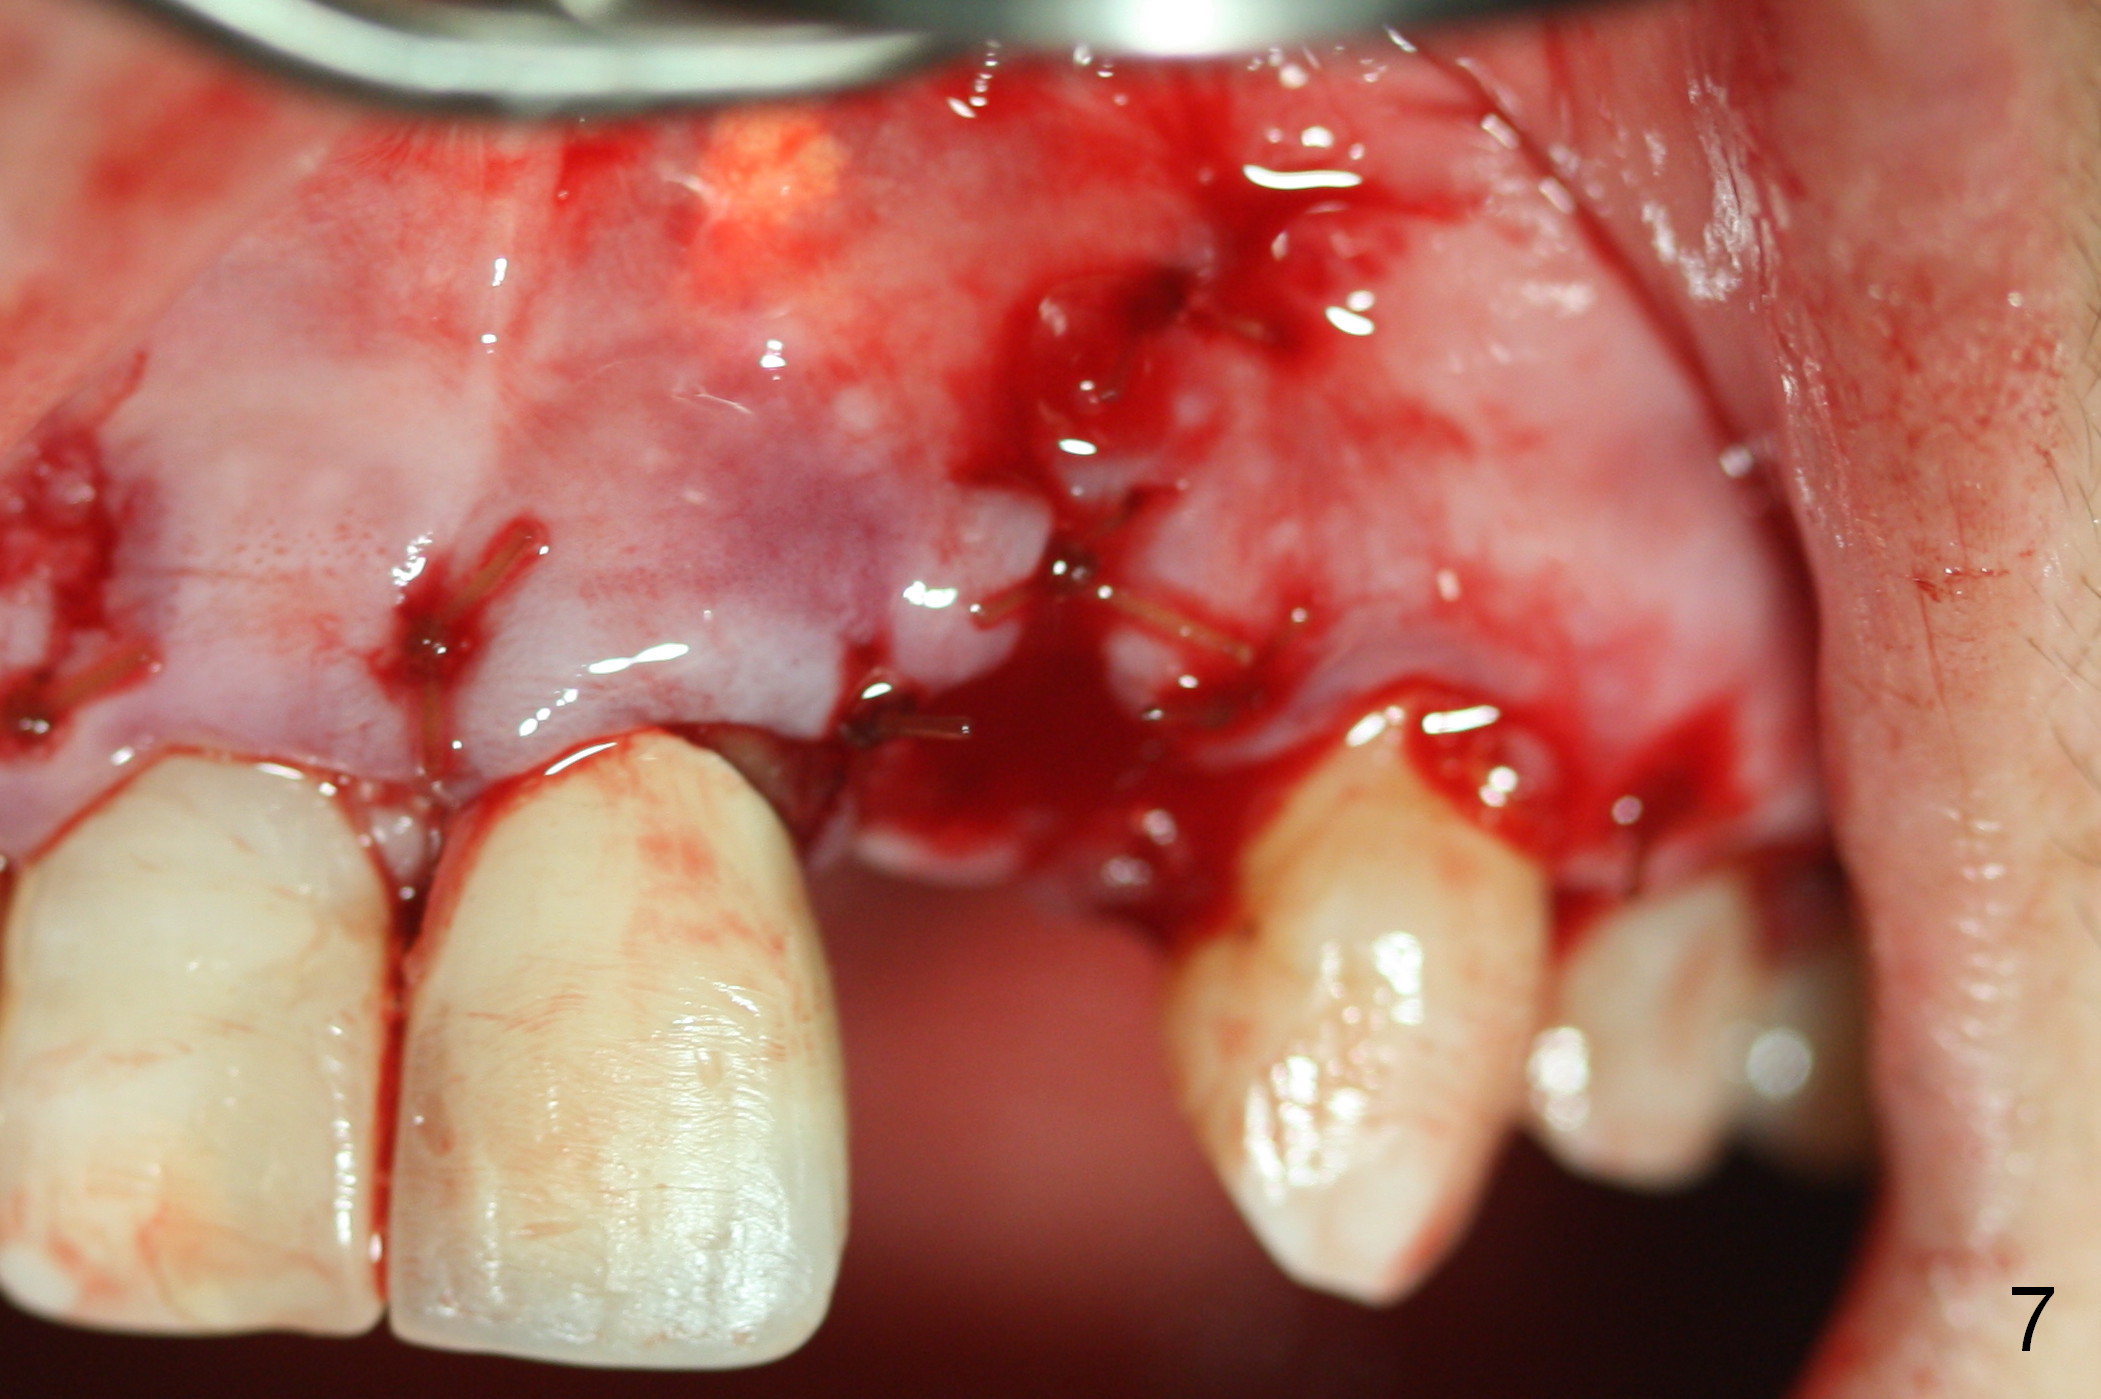

The 57-year-old lady does not like the crown at the site of #10 immediately when it is cemented (Fig.1). When the upper lip is retracted, it appears that the implant is immediately underneath the gingiva (Fig.2 *). It is slightly tender when palpated. The patient refuses CBCT. When the buccal flap is raised, the implant is found to be exposed buccally (Fig.3). When it is removed, the coronal portion of the palatal wall is thin (Fig.4). It appears that there is bone in the mid and apical thirds of the palatal wall, where an osteotomy is initiated using a 1.2 mm pilot drill. When the latter reaches 18 mm from the crest, the nasal floor appears to be perforated. The latter is confirmed by PA (Fig.5). As the osteotomy are increasing in diameter, force is applied as palatally as possible without perforating the palatal wall too much. When a 3.5x20 mm implant is placed (30 Ncm), it is palatal to the labial wall. The defect is filled by allograft and Osteogen, covered by long termed resorption membrane. The buccal flap is sutured (Fig.7). A proposal to place gingival graft is rejected. The implant is shown to have been positioned more or less normally (Fig.8). A removable temporary appliance is fabricated. Periodontal dressing is applied.